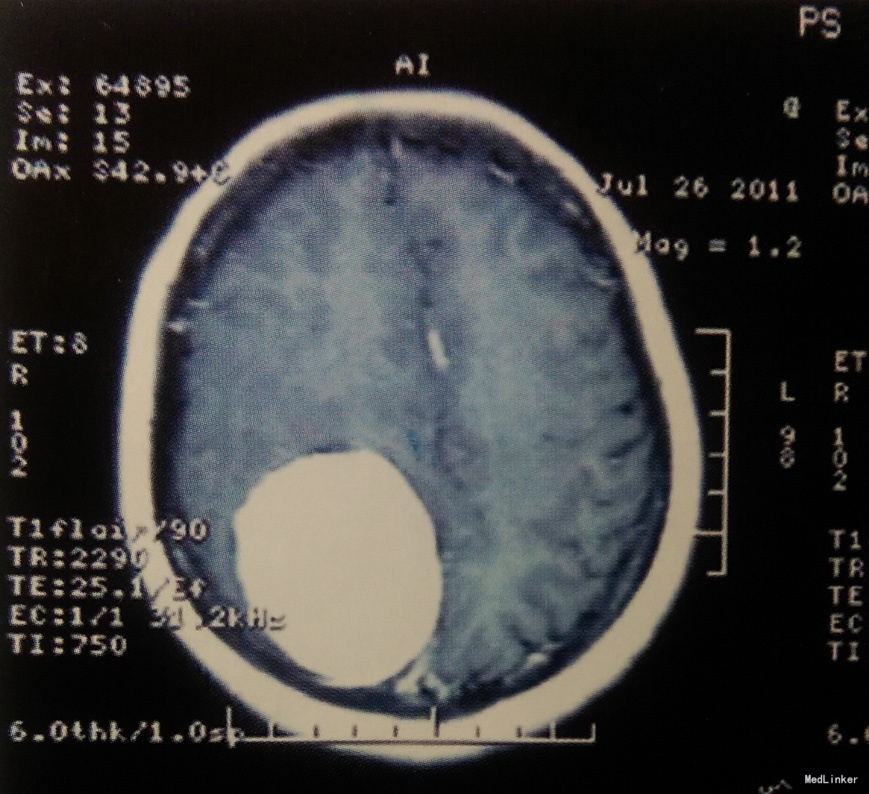

术前影像学检查:颅脑CT及MRI扫描示:右侧额顶部占位,强化效应明显,边界清,考虑脑膜瘤可能。

诊断:右额顶中央前回矢状窦旁脑膜瘤

治疗:在全麻下行开颅探查右额顶中央矢状窦旁巨大肿瘤切除术。